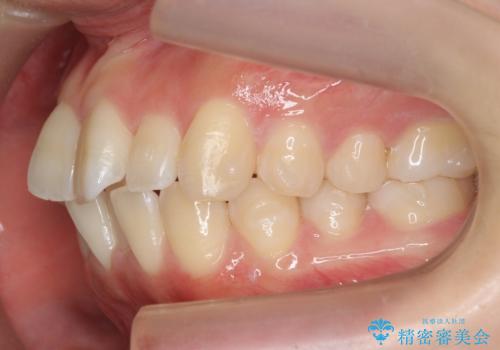

インビザライン モニター治療 前歯のねじれをまっすぐに

- 前歯のねじれを主訴に来院。

インビザラインの部分矯正コースではなく全体矯正コースをご希望でした。

前歯のねじれやがたつきだったため、モニター治療での低価格でのご提案が可能でした。

年齢が10代なこともあり、歯の動きは非常によく、リファインメントなしできれいに並びました。

下の前歯を少し削合して並べています。